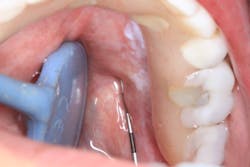

Clinical assessment revealed a white, corrugated lesion lingual to the acrylic of the fixed hybrid prosthesis (figure 2). The lesion measured 5x24 mm and was not able to be scraped off or removed. It was not painful or symptomatic, and no swellings were noted in the sublingual or submandibular lymph node areas (figures 3 and 4).